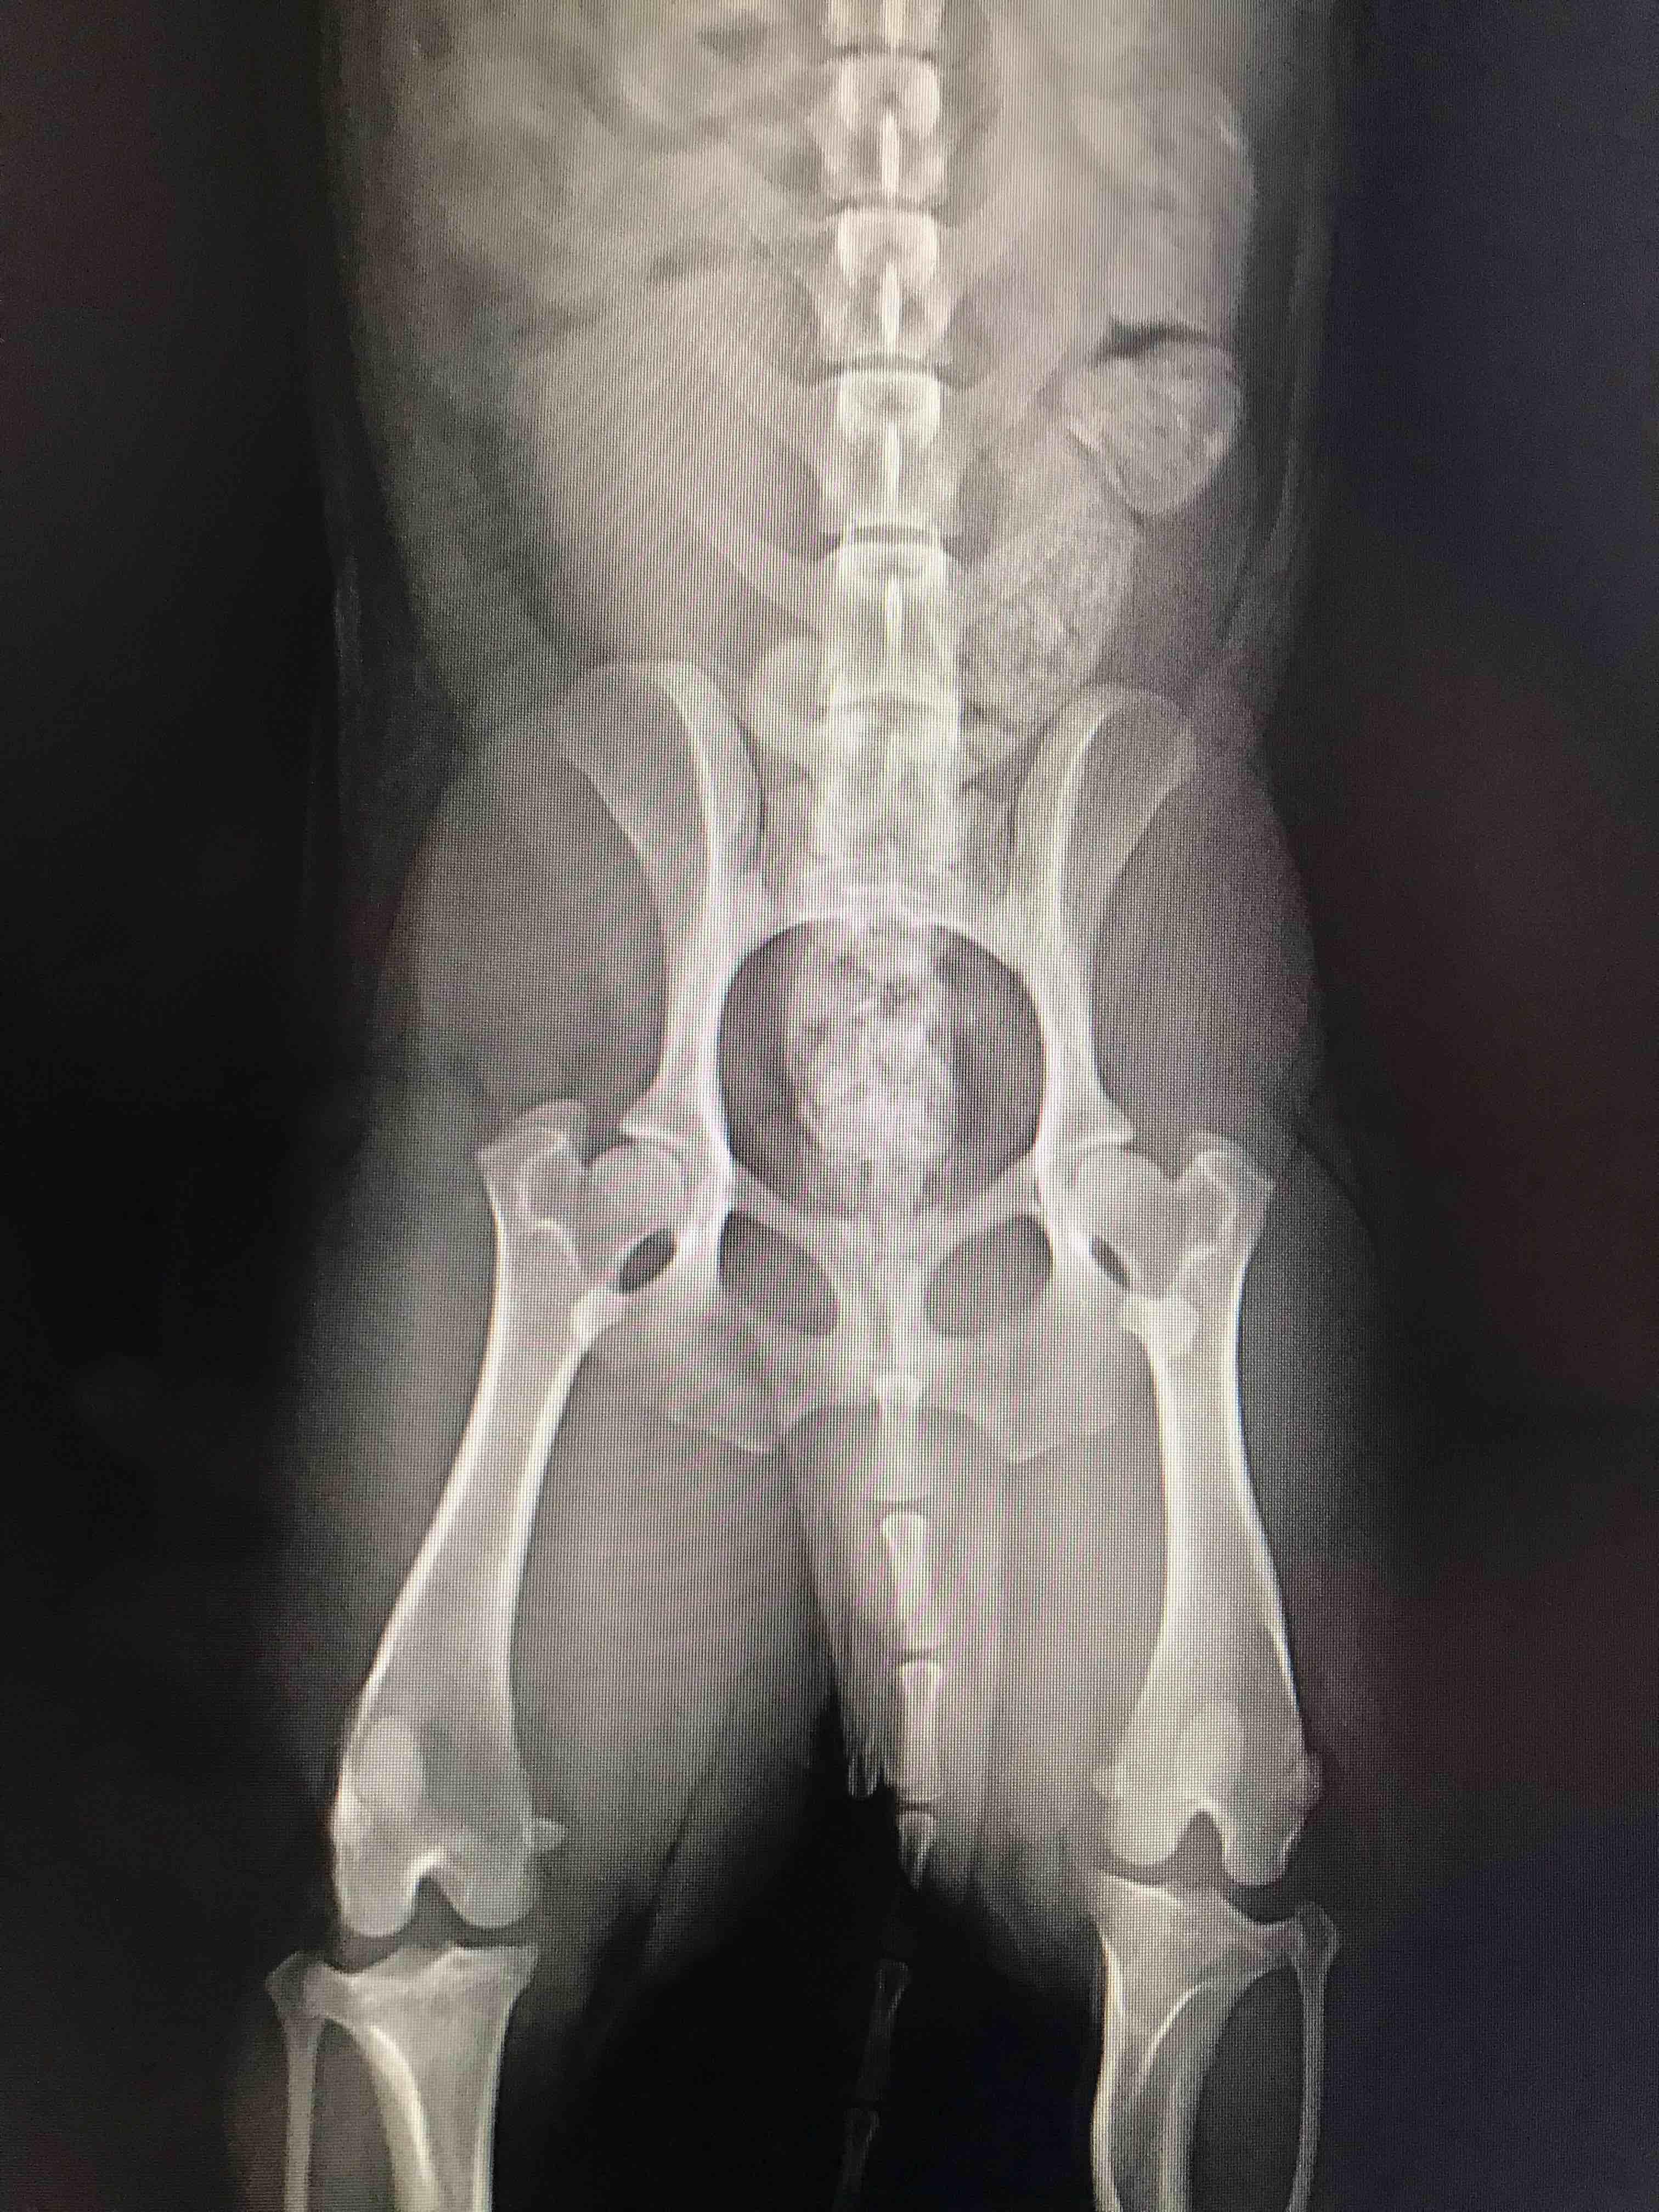

Do my dog's hip x-rays look bad? Should I get a second opinion?

Pet's info: Dog | Mixed Breed | Male | neutered | 3 years and 2 months old | 20.08 lbs

I wanted to know if his hips look bad? I was told not to worry about them but i have a gut feeling his hips don’t look good. Should i have them redone and get a second opinion? Or can you tell from these rads that the hips aren’t to great?

From what I can see his hips look pretty good, there is good coverage of the femoral head by the hip socket, the femoral heads seem to be pretty smooth and rounded, but if you want a second opinion, you can ask your vet for copies of the x-rays or ask them to send them to a veterinary radiologist for an expert eye.